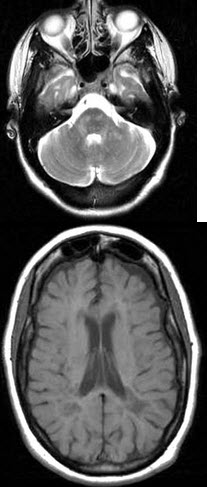

女,56岁,既往有癫痫病史,请结合CT图像选择最可能的诊断( )

A:多发性硬化

B:脑出血

C:脑梗死

D:颅脑肿瘤

E:正常脑实质